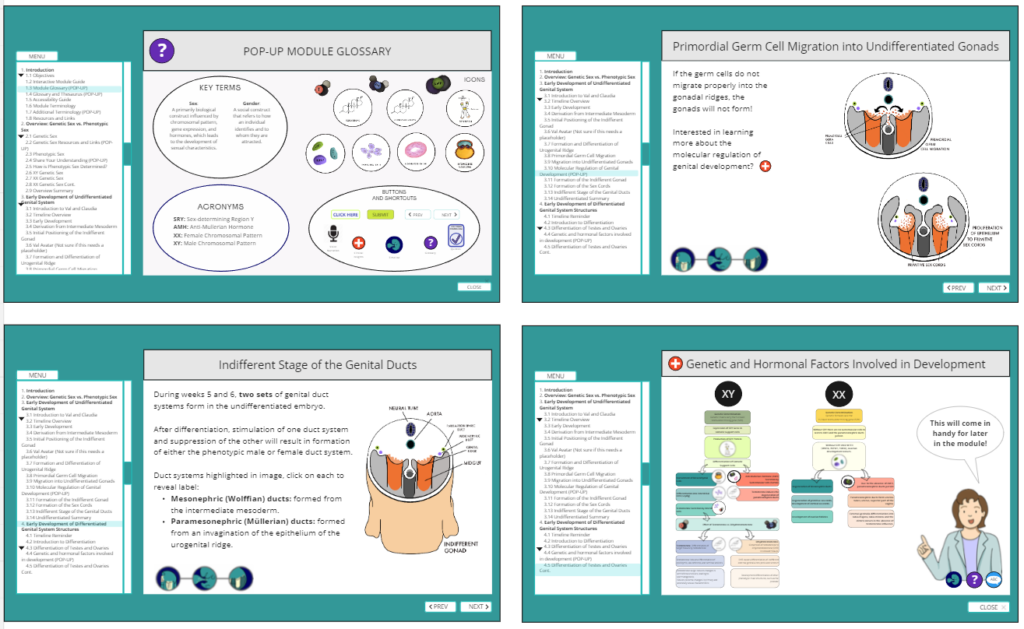

This project, a collaboration between Dr. Valerie O’Loughlin (Indiana University) and my Biomedical Communications capstone team at the UBC HIVE, reimagines how genital embryology is taught. Our goal was to address outdated binary constructs and integrate the latest scientific research into a visually engaging, accessible, and inclusive learning experience for students and educators alike.

Traditional embryology education often oversimplifies genital system development, relying on binary models that fail to reflect biological diversity. Our interactive module addresses this gap, offering a comprehensive, research-backed exploration of genital development with a focus on inclusivity and scientific accuracy. This approach promotes a deeper understanding of human biology while preparing students for real-world healthcare scenarios that require both medical knowledge and empathy.

Developed over 14 months (September 2023 – November 2024), this project brought together a multidisciplinary team of students, faculty, and medical professionals. Using industry-standard tools such as Adobe Illustrator, Photoshop, Animate, and Articulate 360, we created anatomically accurate visuals and animations. The module follows Universal Design for Learning (UDL) principles and Mayer’s principles of multimedia learning, ensuring an accessible and effective educational experience.

Development of the Genital System